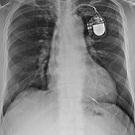

Un stimulateur cardiaque permet de délivrer des impulsions électriques au cœur, l’accélérant par exemple si besoin. Le nombre d’implantations de ces stimulateurs augmente régulièrement depuis plus de dix ans. Plus de 50 000 patients bénéficient chaque année de l’implantation d’un stimulateur cardiaque en France. Le vieillissement de la population est l’un des facteurs du nombre grandissant de patients implantés sur l’ensemble du territoire.